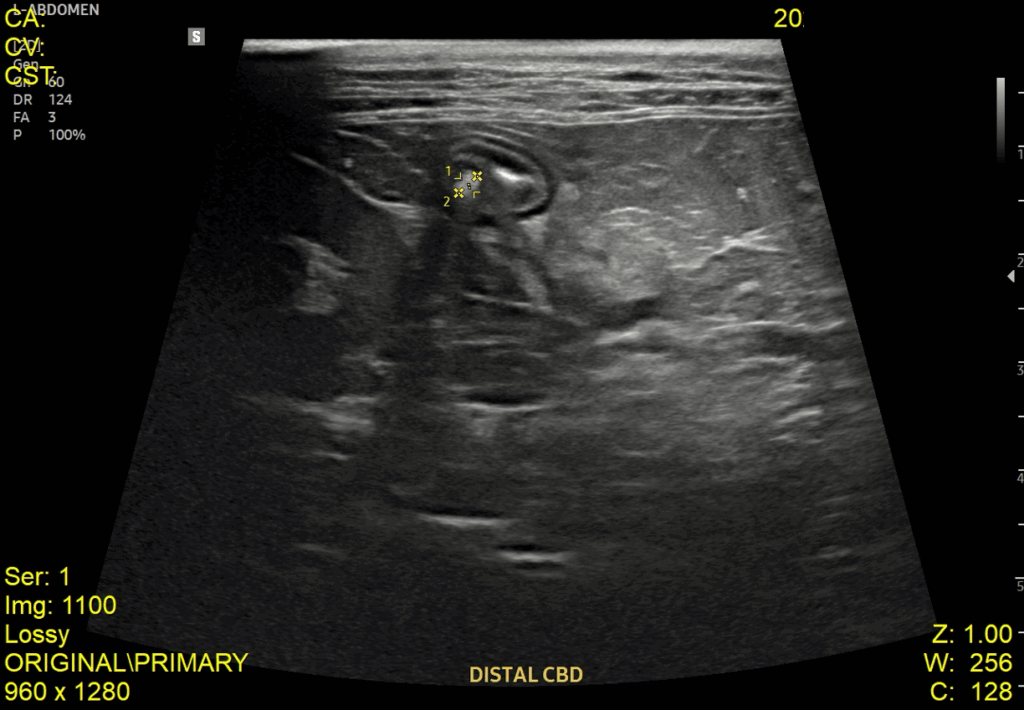

이어서 진행한 복부 초음파 검사에서는 췌장염 소견과 함께 위벽 및 일부 장 근층 비후가 관찰되었고, 담낭관(Cystic duct)과 총담관(CBD)이 심하게 확장되어 있으며 내강 내 슬러지가 확인되었습니다. 또한 담낭 내에는 중등도의 슬러지와 담석이 있었고, 간 내 담도 결석과 전반적인 간 에코 증가도 함께 확인되었습니다.

내원당시 복부초음파 검사 결과 / 출처: 강서YD동물의료센터